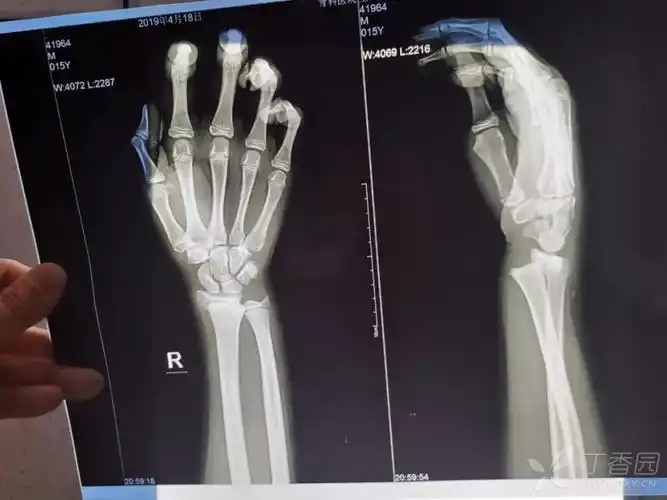

青少年桡骨远端骨骺分离骨折